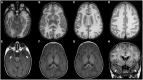

Macrocephaly affects up to 5% of the pediatric population and is defined as an abnormally large head with an occipitofrontal circumference (OFC) >2 standard deviations (SD) above the mean for a given age and sex. Taking into account that about 2-3% of the healthy population has an OFC between 2 and 3 SD, macrocephaly is considered as "clinically relevant" when OFC is above 3 SD. This implies the urgent need for a diagnostic workflow to use in the clinical setting to dissect the several causes of increased OFC, from the benign form of familial macrocephaly and the Benign enlargement of subarachnoid spaces (BESS) to many pathological conditions, including genetic disorders. Moreover, macrocephaly should be differentiated by megalencephaly (MEG), which refers exclusively to brain overgrowth, exceeding twice the SD (3SD-"clinically relevant" megalencephaly). While macrocephaly can be isolated and benign or may be the first indication of an underlying congenital, genetic, or acquired disorder, megalencephaly is most likely due to a genetic cause. Apart from the head size evaluation, a detailed family and personal history, neuroimaging, and a careful clinical evaluation are crucial to reach the correct diagnosis. In this review, we seek to underline the clinical aspects of macrocephaly and megalencephaly, emphasizing the main differential diagnosis with a major focus on common genetic disorders. We thus provide a clinico-radiological algorithm to guide pediatricians in the assessment of children with macrocephaly.